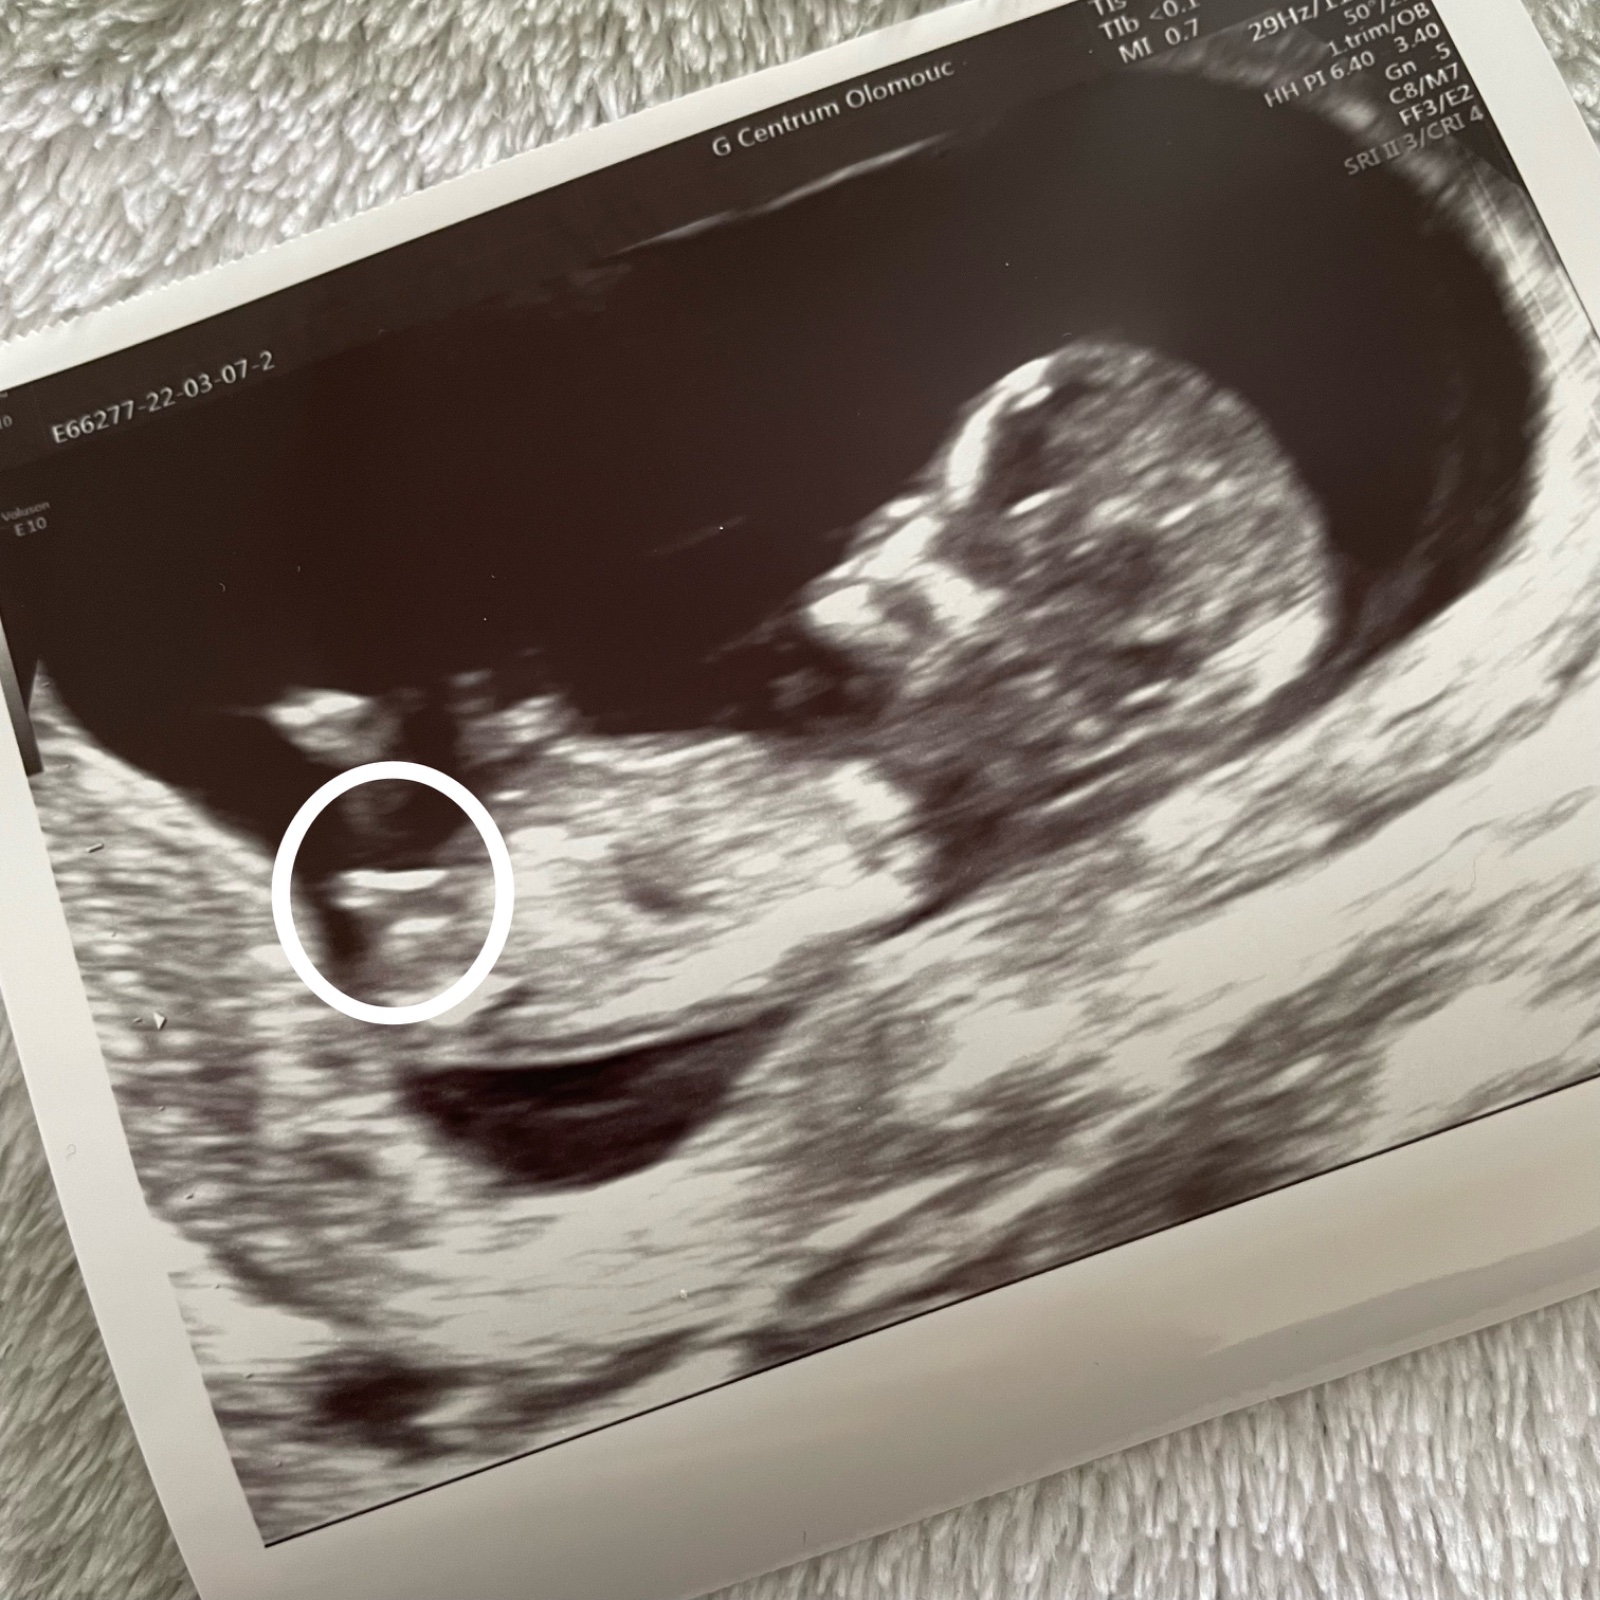

jedná se prosím o pohlavní hrbolek?

Foto je z 13. tt. Lze podle něj už nyní tipnout pohlaví? 😊

co lze z fotografie odhadovat (a vždy je lepší vyšetření v reálném čase), vypadá to na holčičku (cca na 90 %). Určitě před nákupy vyčkejte na potvrzení v II. trimestru. 😉